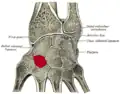

Cross section of wrist (thumb on left). Trapezoid shown in red (labelled as "Lesser Multang").

Cross section of wrist (thumb on left). Trapezoid shown in red (labelled as "Lesser Multang").